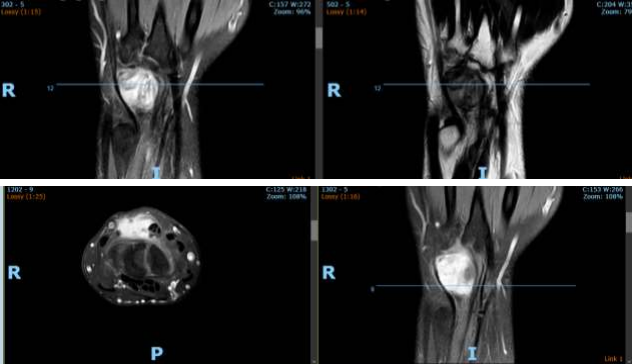

The patient had a solid hypoechoic lobulated mass lesion measuring 27x16mm on the dorsal aspect of his left wrist. The diagnosis was a giant cell tumor and soft tissue sarcoma, and fur-ther investigations were advised. X-rays showed a soft tissue shadow in the lateral view, but no bony abnormalities were noted. MRI scans revealed an irregular, intensely enhancing soft tissue mass at the wrist's dorsal aspect, interposed between the 4th and 5th extensor tendon compartments. The MRI findings were consistent with a benign soft tissue neoplasm.

The features of nodular fasciitis on ultrasound and magnetic resonance imaging (MRI) are non-specific, with the lesions appearing as well-circscribed, round to oval masses. Signal intensity of the condition is variable, with intramuscular lesions appearing mildly inhomo-geneous and hyper intense to skeletal muscle on T1-weighted spin-echo images, and subcu-taneous lesions being markedly hypo intense to skeletal muscle on all spin-echo sequences and appearing homogeneous in texture. High cellularity and micro-vessel density may di-rectly influence the early enhancement after intravenous gadolinium injection and compact cellularity with a prominent capillary network. A myxoid pattern may be responsible for the enhancement on MRI (7,8).

Figures 1,2,3,4,5,6

Figure 3